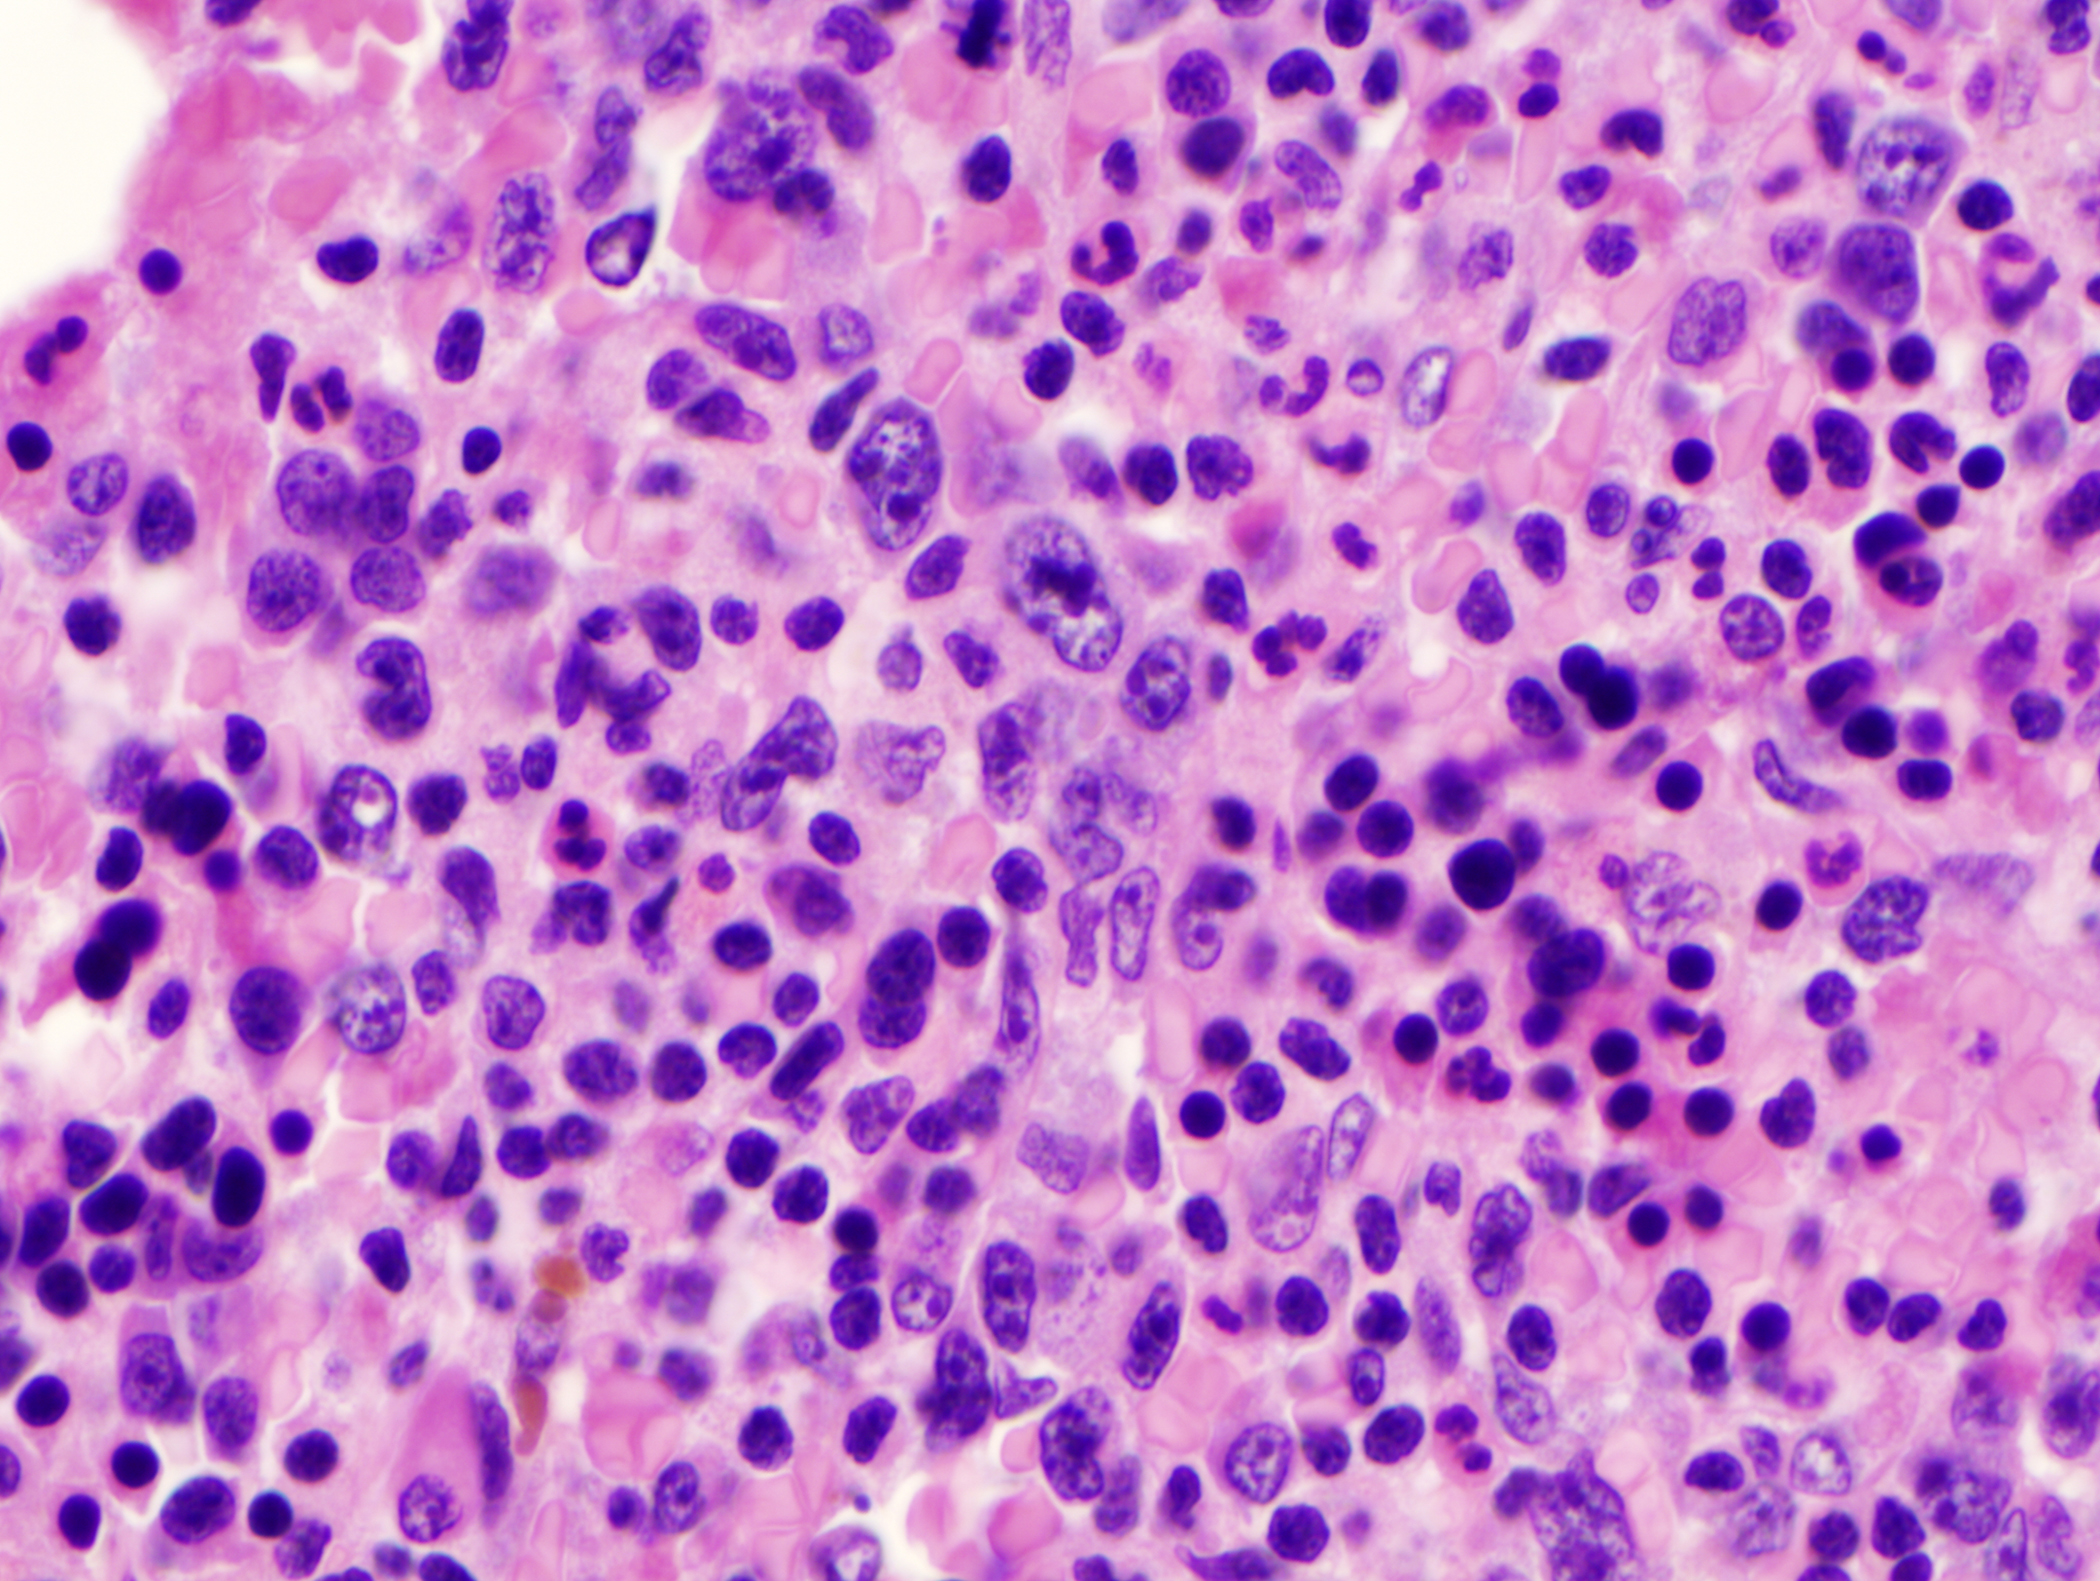

The labyrinth of pyrexia of unknown origin: A case of intravascular B cell lymphoma